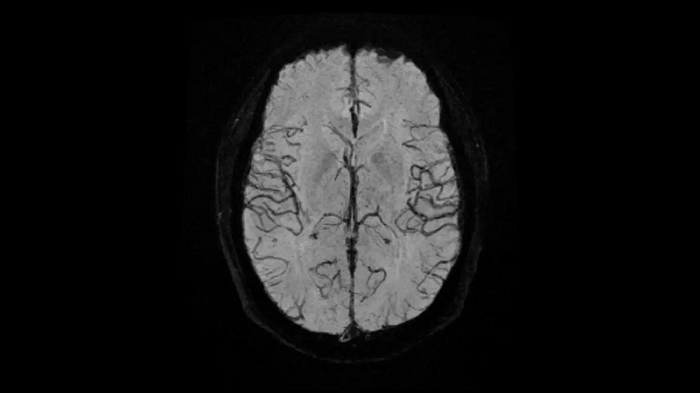

Head

EPI-based 3D SWI

A new approach towards susceptibility-weighted imaging founded on 3D EPI allows highly resolved and high-quality depiction of cranial veins on MAGNETOM Free.Max.

Image Courtesy: University Hospital Erlangen, Germany | Image-ID: 4aaaa0297